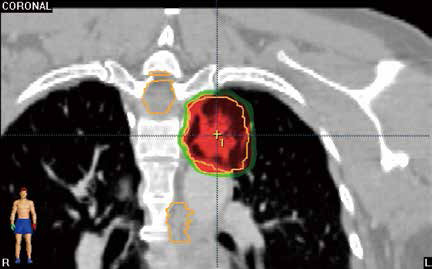

不宜手术的中央型早期老年NSCLC 立体定向放…

不宜手术的中央型早期老年NSCLC 立体定向放…

2019-04-17 15:07:04

加拿大玛嘉烈公主癌症中心Bezjak等报告,治疗不宜手术的中央型早期非小细胞肺癌(NSCLC)老年患者时,当立体定向放疗(SBRT)的最大耐受剂量(MTD)为12 Gy/f时,可带来较低的剂…